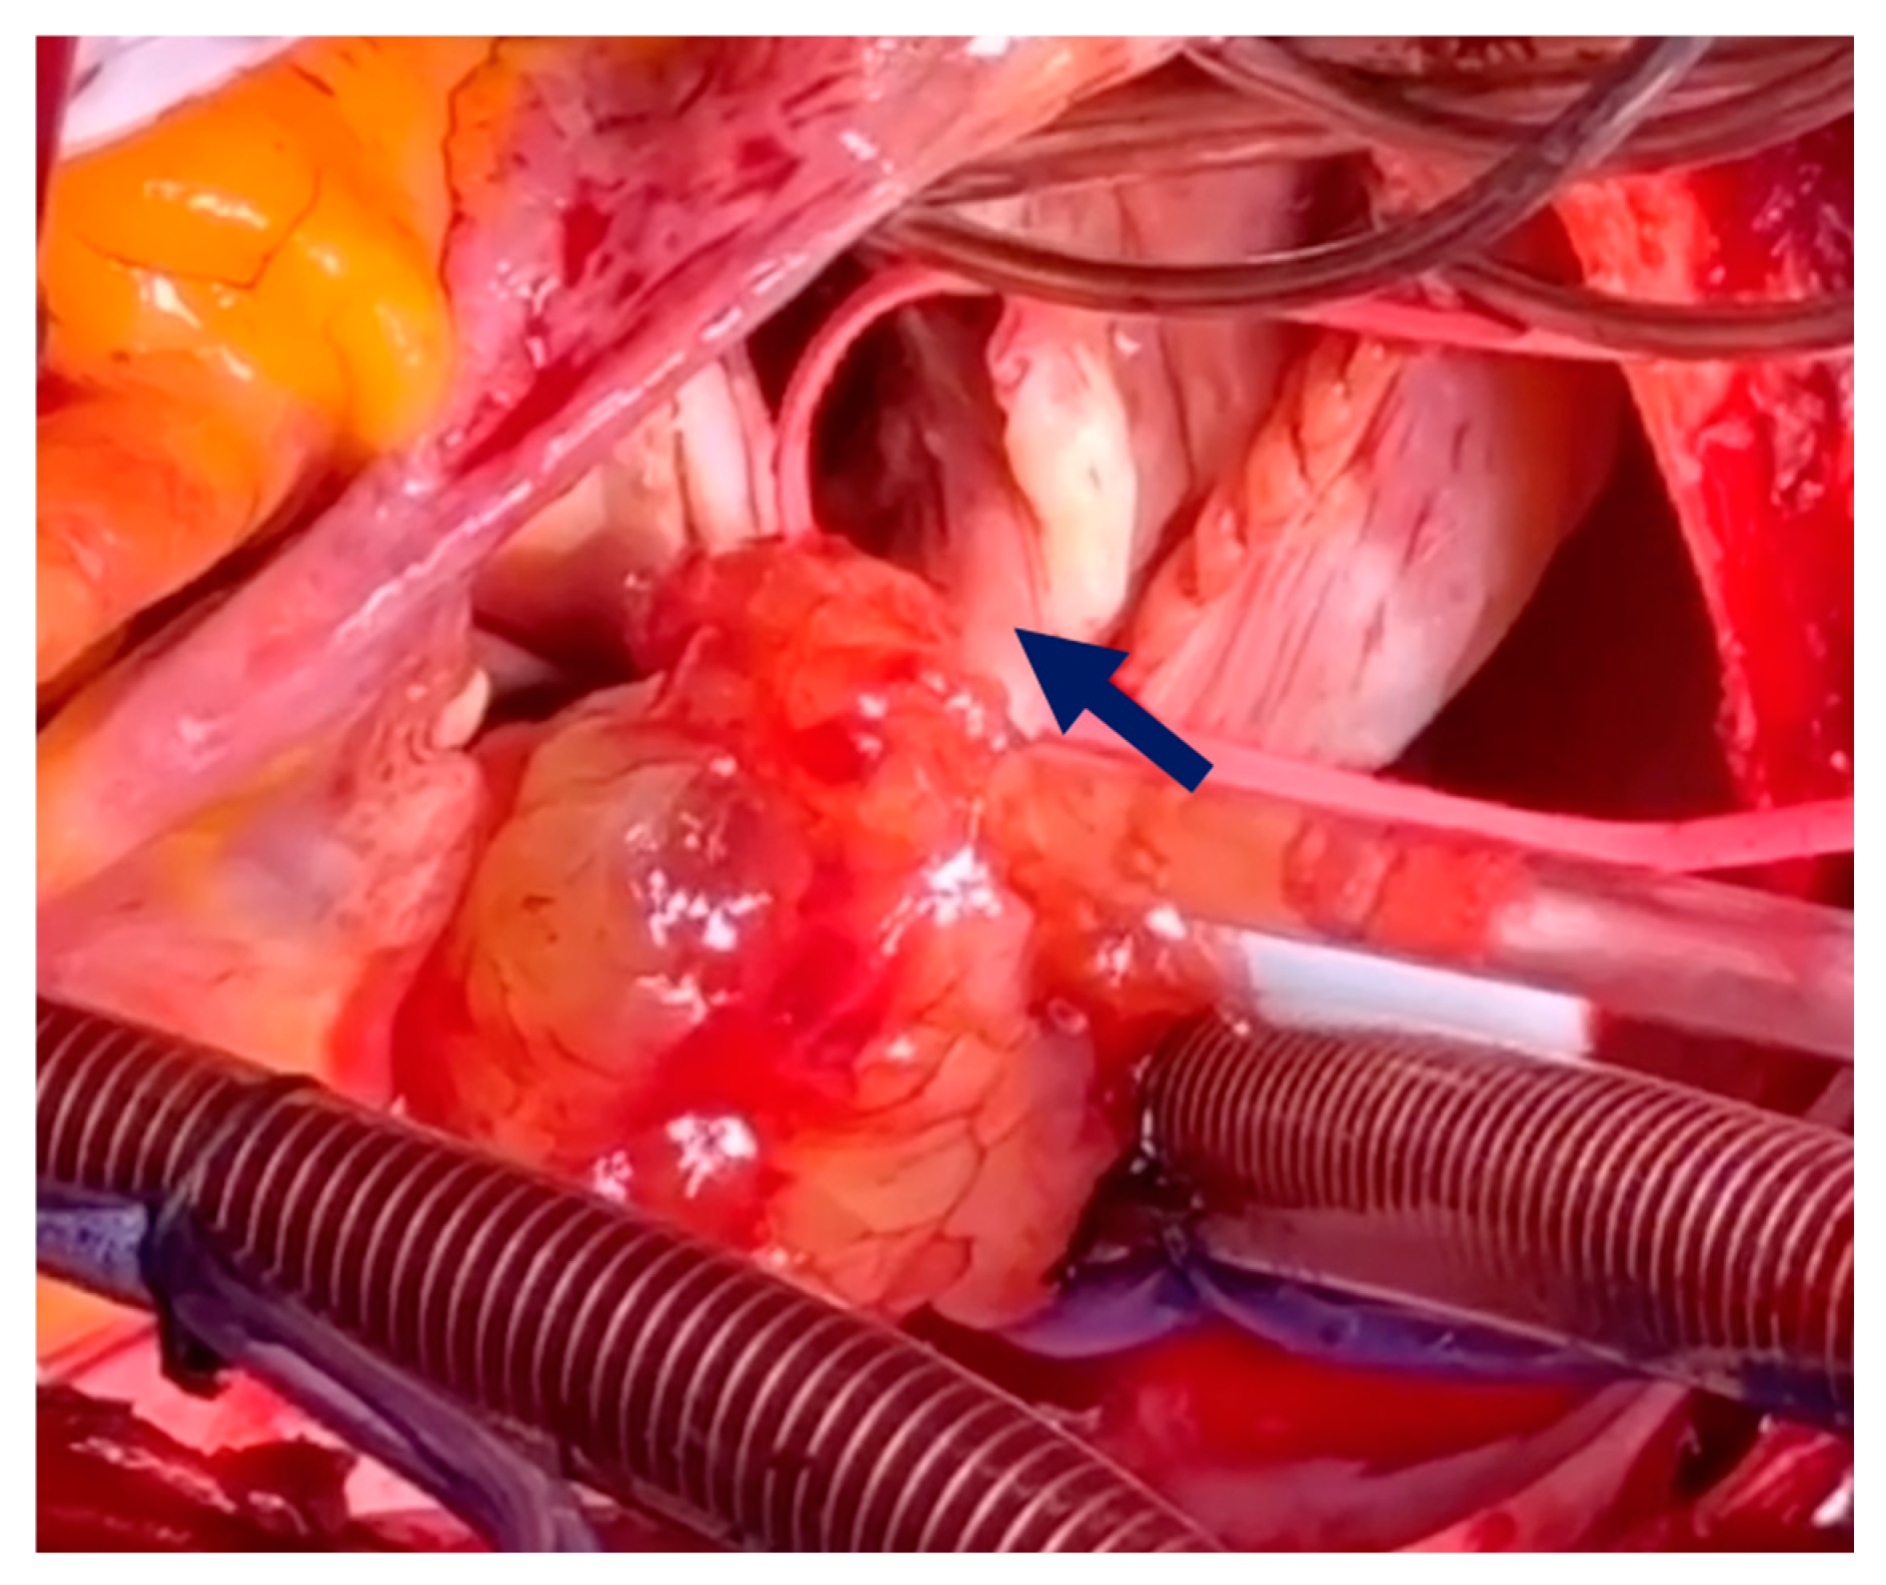

Pre-operative cardiac magnetic resonance imaging (MRI) and transesophageal echocardiogram (TEE) revealed a myxoma measuring 46 mm × 37 mm × 30 mm in the right atrium. The base of the myxoma, located around the basal posterior wall of the right atrium, appeared to extend to the tricuspid valve and right ventricle (Figure 1 and Figure 2). Despite the localization and considerable size of the myxoma, there was no significant tricuspid valve insufficiency, and the function of both the left and right ventricles remained within normal parameters. The patient was evaluated for open-heart surgery involving the removal of a myxoma, with consideration for tricuspid valve replacement.

The intervention was conducted with the patient under general anesthesia, with intubation and hemodynamic monitoring. The patient was fully heparinized, and cannulation was performed via arterial access through the ascending aorta and bicaval venous access. After the initiation of cardiopulmonary bypass, the right atrium was opened. The large myxoma originated from the apex of the papillary muscle, extending toward the posterior and septal leaflets, with chorda tendineae encroaching upon the posterior leaflet (Figure 3).

Figure 3. Cardiac myxoma extending toward the posterior leaflet chord. The blue arrow indicates the posterior leaflet chord.